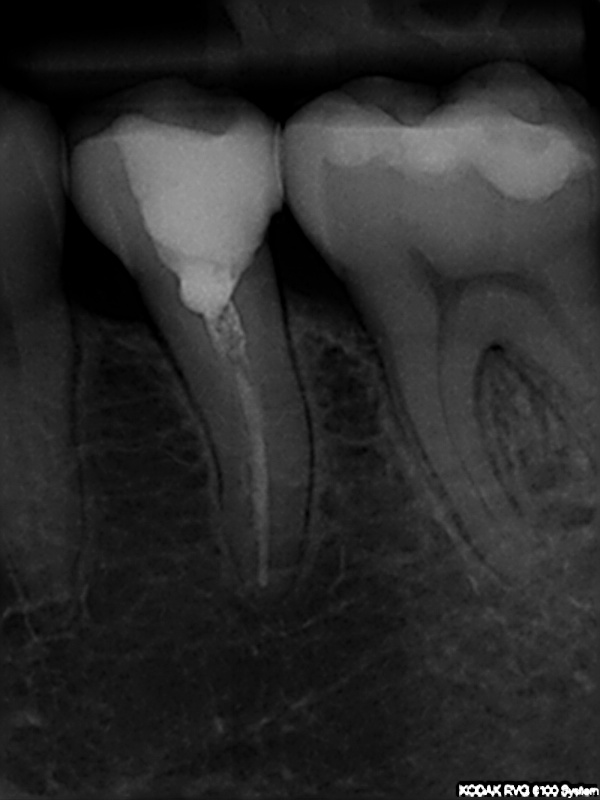

und wieder ein Recall

Ausgangssituation